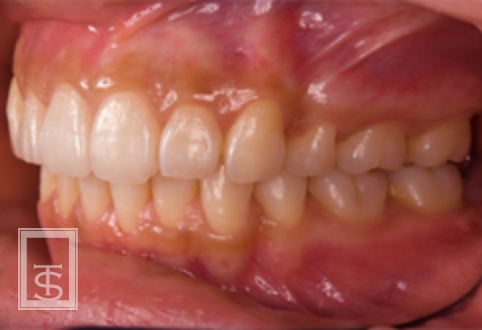

- 静的治療

- 歯の移動後の安定を図ります。

この時は保定装置という取り外し可能な装置を使用します。